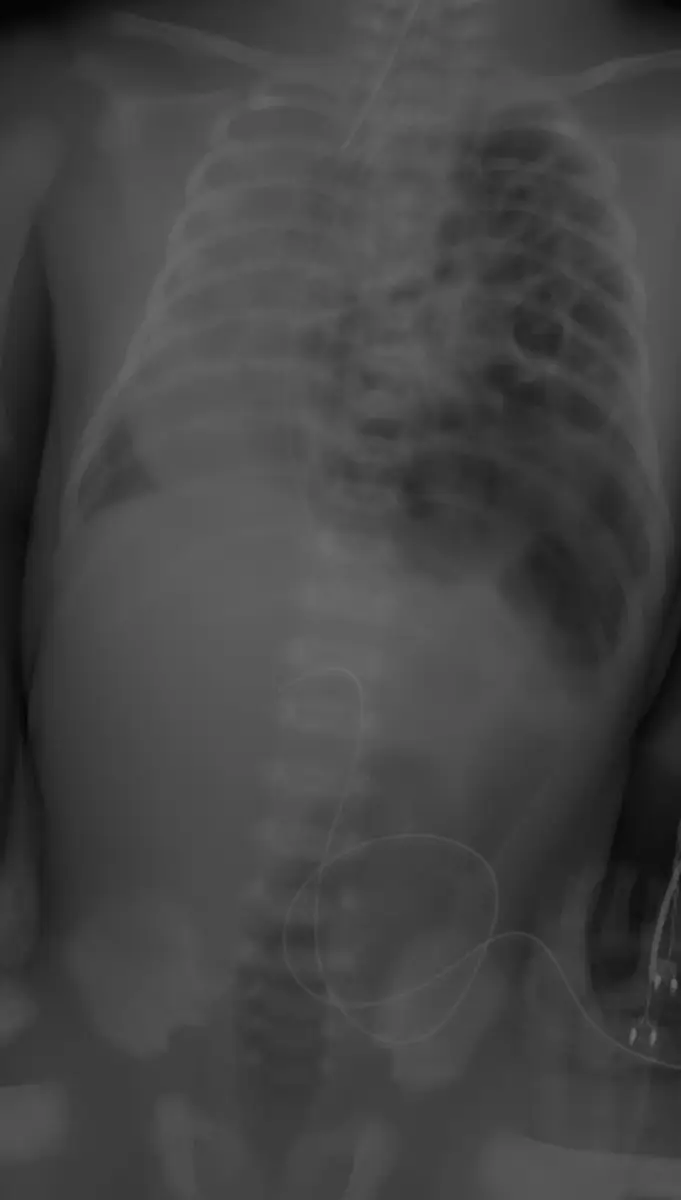

足月產新生兒因呼吸急促住進新生兒加護病房,胸腹部X光如附圖,則最可能的診斷為下列何者?

本題胸腹部 X 光(正位,AP view)顯示以下重要發現:

- 左側胸腔:可見多個氣體充填的腸管影(bowel gas loops)分布於左側胸腔,取代了正常肺組織的位置,呈現不均勻的透亮(黑色)氣泡狀影像。

- 縱膈(mediastinum)與心臟:心臟影像相對偏向右側,提示縱膈向右移位。

- 右肺:相對保有部分含氣的肺組織影像。

- 腹部:腹部氣體較少(腹腔內腸管疝入胸腔,導致腹腔相對空虛)。

- 橫膈:左側橫膈輪廓不清楚,提示橫膈缺損。

上述影像特徵——左胸腔充滿腸管氣泡影、心臟右移、腹腔氣體減少——符合先天性橫膈疝脫(congenital diaphragmatic hernia, CDH) 的典型 X 光表現,尤其是最常見的 左側 Bochdalek 疝脫。